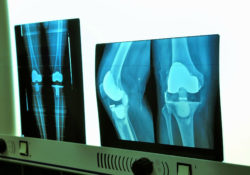

Zimmer knee implant problems may lead to revision surgeryZimmer knee implant problems have become a recent concern in the United States medical community and patient population, with a recent recall of one of its implant components.

• Radiolucent Lines: These are lines or gaps between the implant and the bone, which appear on X-ray images. When the tibial plate loosens and allows for these gaps to form, it is a sign of “poor seating”. This means the implant component has shifted from its original position, and is often an early sign of device loosening.